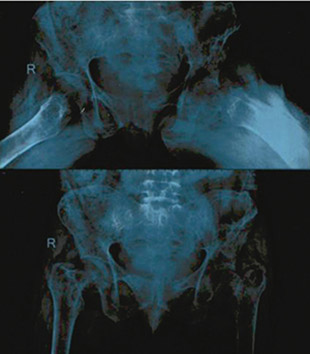

She underwent focussed neck exploration via minimally invasive approach under GA. Intra-operatively (findings as shown in Figures 3‒5), a nodular lesion was noted over left inferior thyroid gland. In view of suspected intra thyroid ectopic location of parathyroid, a left hemithyroidectomy was done. Intra-operative frozen Section was sent, however there was no parathyroid gland visualised in the excised tissue. Incision was then extended inferiorly and on further exploration, left inferior parathyroid lesion of size 1.5×1.5 cm was found at the intra-thymic location, which was confirmed by repeat frozen section after excision. Left recurrent laryngeal nerve (RLN) and left external laryngeal nerve (ELN) were seen and preserved.

Figure 3. Focussed neck exploration showing relevant anatomy – the thyroid gland, left Recurrent laryngeal nerve (RLN), nodular lesion over inferior pole of left thyroid

Figure 4. Intra-thymic Left inferior parathyroid – seen after left hemithyroidectomy